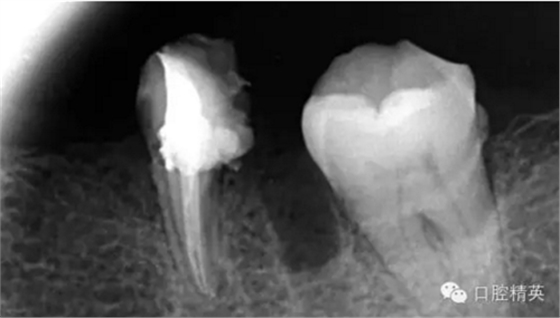

疏通其余三根30分鐘。

近中試尖,超出,這是沒有很好的把握工作長(zhǎng)度,這是自己在預(yù)備時(shí)可能出現(xiàn)超預(yù)備的情況,所以以后機(jī)括預(yù)備一定要注意,防止超預(yù)備,否則會(huì)導(dǎo)致術(shù)后疼痛。